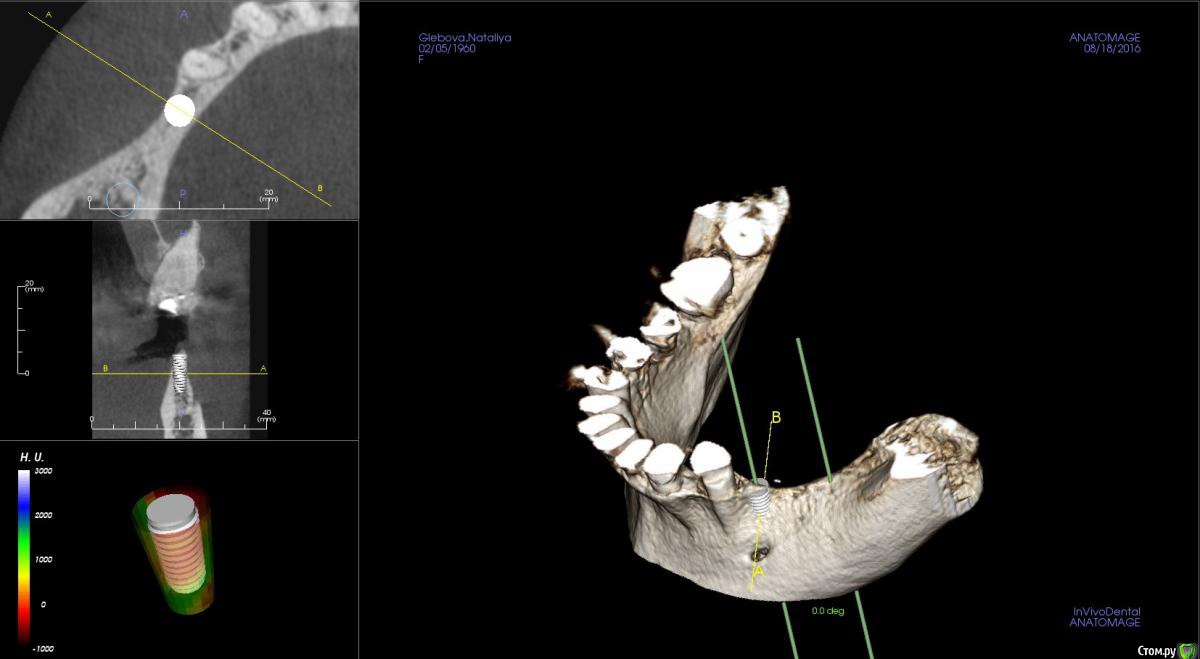

kamranchick Опубликовано 23 августа, 2016 Поделиться Опубликовано 23 августа, 2016 Господа, как посоветуете поступить на 4 сегменте?Какая методика здесь будет предсказуема, и возможно ли установка сразу болтов, так как пациентка уезжает на 8 месяцев в командировку, смущает что менталис рядом и очень тоненький биотип десны Ссылка на комментарий